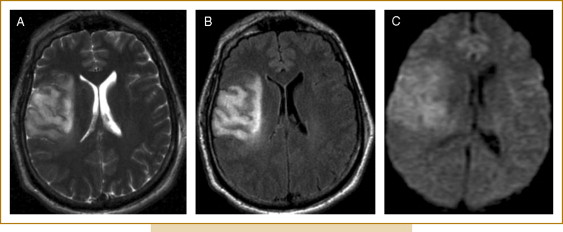

1. 신속한 평가 및 진단: 뇌경색 초기증상과 징후를 신속하게 인식하는 것은 적시에 개입하고 환자 결과를 개선하는 데 필수적입니다. 의료 전문가는 NIHSS(National Institutes of Health Stroke Scale)와 같은 도구를 사용하여 잠재적인 뇌경색 환자를 신속하게 평가하고 컴퓨터 단층 촬영(CT) 스캔 또는 자기 공명 영상(MRI)을 포함한 진단 테스트를 시작하여 진단을 확인하고 유형을 결정해야 합니다.

2. 즉각적인 치료: 뇌경색이 진단되면 뇌 손상을 최소화하기 위해 가능한 한 빨리 치료를 시작해야 합니다. 특정 치료는 뇌출혈 유형에 따라 다릅니다(허혈성 또는 출혈성) 다음과 같이 분류할 수 있습니다.

• 허혈성 뇌졸중(혈전이 뇌로 가는 혈류를 차단하여 발생)의 경우 증상이 시작된 후 처음 4.5시간 이내에 조직 플라스미노겐 활성화제(tPA)와 같은 혈전 용해 약물을 투여하면 결과를 크게 개선할 수 있습니다. 경우에 따라 기계적 혈전 제거술과 같은 혈관 내 절차를 수행하여 혈전을 제거하고 혈류를 회복할 수도 있습니다.